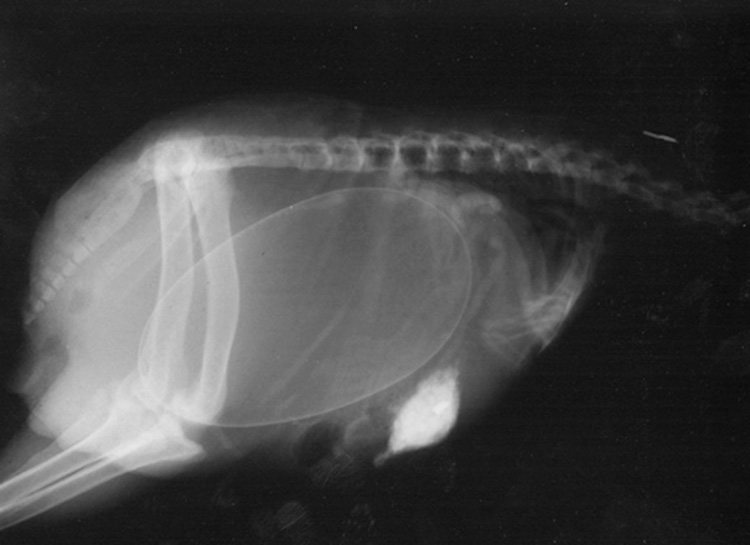

3 – Chatte enceinte. Les chattes peuvent tomber enceinte à 4 mois. À environ 45 jours de grossesse, les squelettes des chatons sont assez formés pour être visibles aux rayons X.